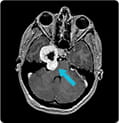

Trigeminal Schwannoma

Scans of a 17-year-old girl who complained of headaches showed a large trigeminal schwannoma at the base of the skull. The tumor had two portions, separated by the petrous bone and the brain covering. Read how UPMC surgeons were able to avoid any damage to the nerves in and around the petrous bone and the carotid artery by using several techniques, including EEA, to completely remove the tumor.